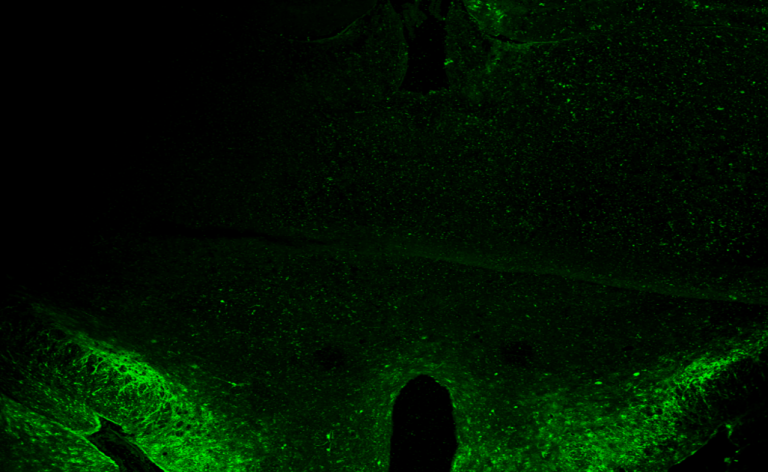

Et si la clé de la longévité cellulaire déclenchait l’obésité ?

Et si la clé de la longévité cellulaire déclenchait l'obésité ? Le projet THALATEL révèle un paradoxe troublant : en cherchant à prolonger la vie…